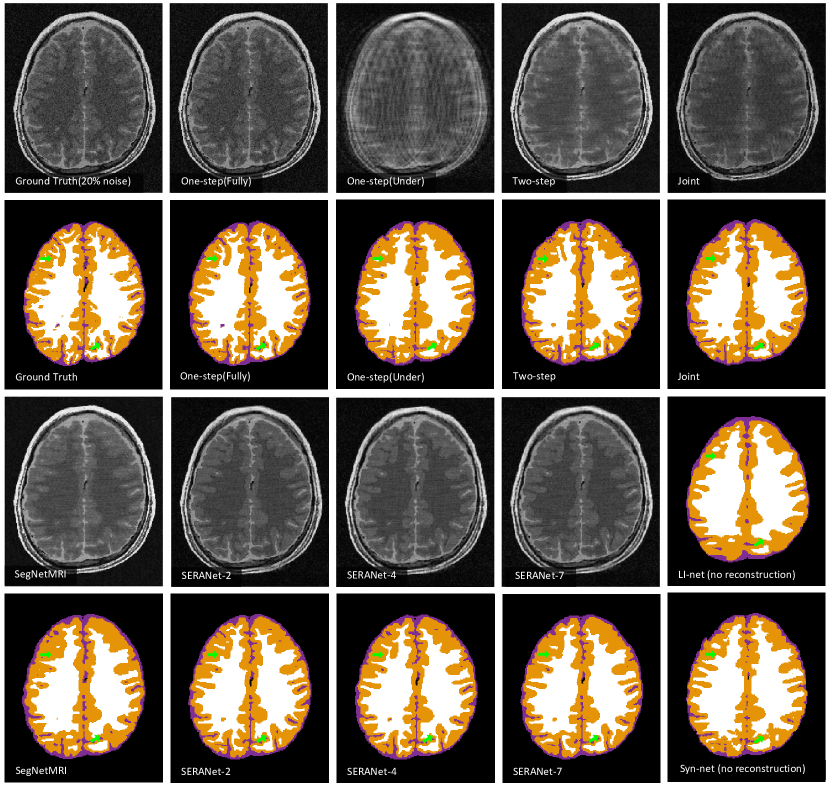

For visualization, we also train an One-step model that takes input as zero-filling images (inverse Fourier transform of under-sampled -space data) and outputs the segmentation maps. We visualize segmentation results and reconstructed images of models trained by 20% noise data in Figure 3. Our method SERANet predicts more accurate anatomical segmentation details and clearer image contrasts compared to Two-step and Joint. This shows SERANet overcomes the interference with noisy input by using the attention module.

We provide qualitative and quantitative comparisons to three state-of-the-art algorithms: LI-net[10] Syn-net[10], and SegNetMRI[11]. We also compare to the One-step model. We list the performance of SERANet-7 that with 7 reconstruction blocks and SERANet-2 that with 2 reconstruction blocks. The results of all methods are reported in Table 2. We also list whether the method is pretrained and what loss the method uses to optimize in column 2 and 3, respectively. For LI-net and Syn-net, since they perform segmentation from fully-sampled data as a warm start, we consider this as a pretraining technique. We observe that SERANet-2 and SERANet-7 consistently outperform the three state-of-the-art approaches for both 10% and 20% noises. Additionally, the Diceβs scores drop more for the SegNetMRI when noise level increases compared to SERANet, which may be due to the fact that SegNetMRI contains information from the noisy ground truth images. Example segmentation results are shown in Figure 4. Improvements of SERANet-7 on detailed anatomy structure are highlighted by the green arrows.

In this section, we provide additional quantitative results. We demonstrate the comparison results of our SERANet and other approaches on data with (Figure 8) white Gaussian noise and data with noise (Figure 9). For LI-net and Syn-net, we only show their segmentation results since they bypassed the reconstruction step. For our SERANet, we present the results of SERANet-2, SERANet-4 and SERANet-7 here.